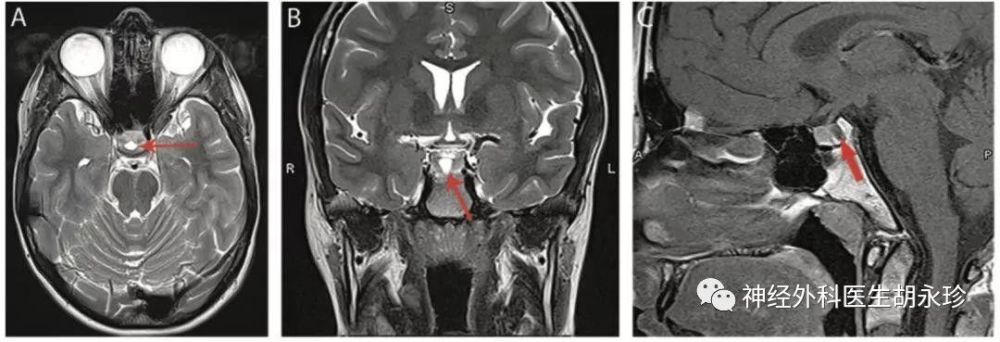

刘全义,男,43岁,鞍区占位,rathke裂囊肿

图片尺寸1563x1113